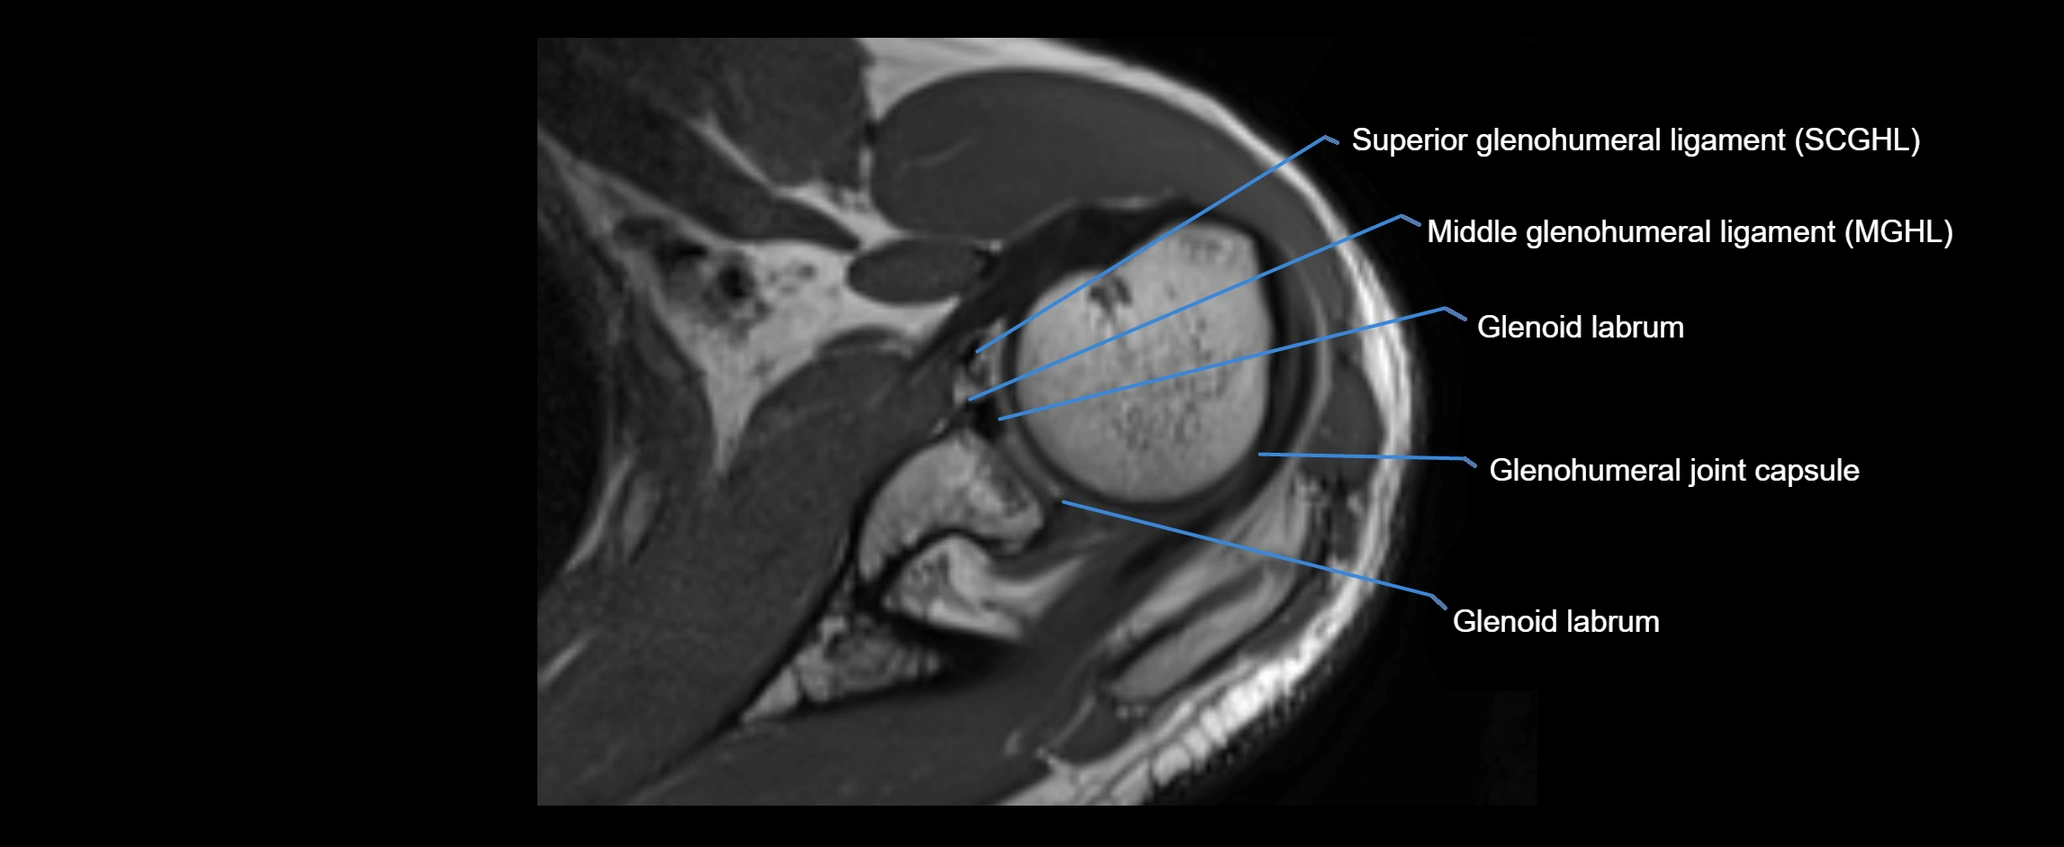

CT image

image